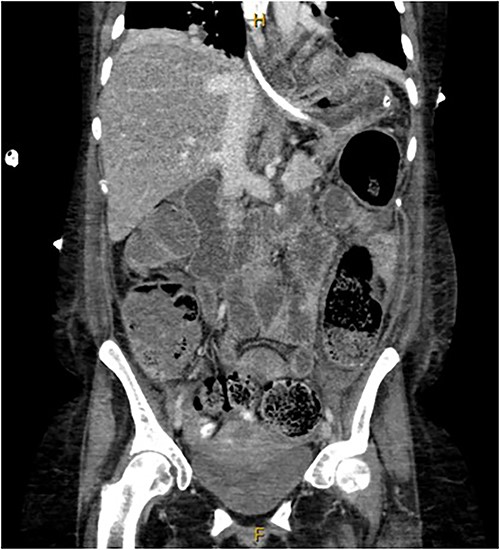

A provisional diagnosis of a ‘bowel obstruction’ was made and she was admitted to hospital for conservative management with nasogastric drainage, intravenous hydration, and aperients. Over the following 24 h, her abdominal pain remained severe and further surgical review was sought. At this stage she exhibited a distended, firm, exquisitely tender abdomen. A repeat CT at this time once again demonstrated faecal loading, normal bowel wall enhancement, and no perforation (Figs 1 and 2). At this stage she was fasted and consented for an exploratory laparotomy under general anaesthesia. She proceeded to theatre after reversal of her INR with prothrombinex and vitamin K.

Coronal view of CT abdomen demonstrating normal large bowel wall enhancement with faecal loading.